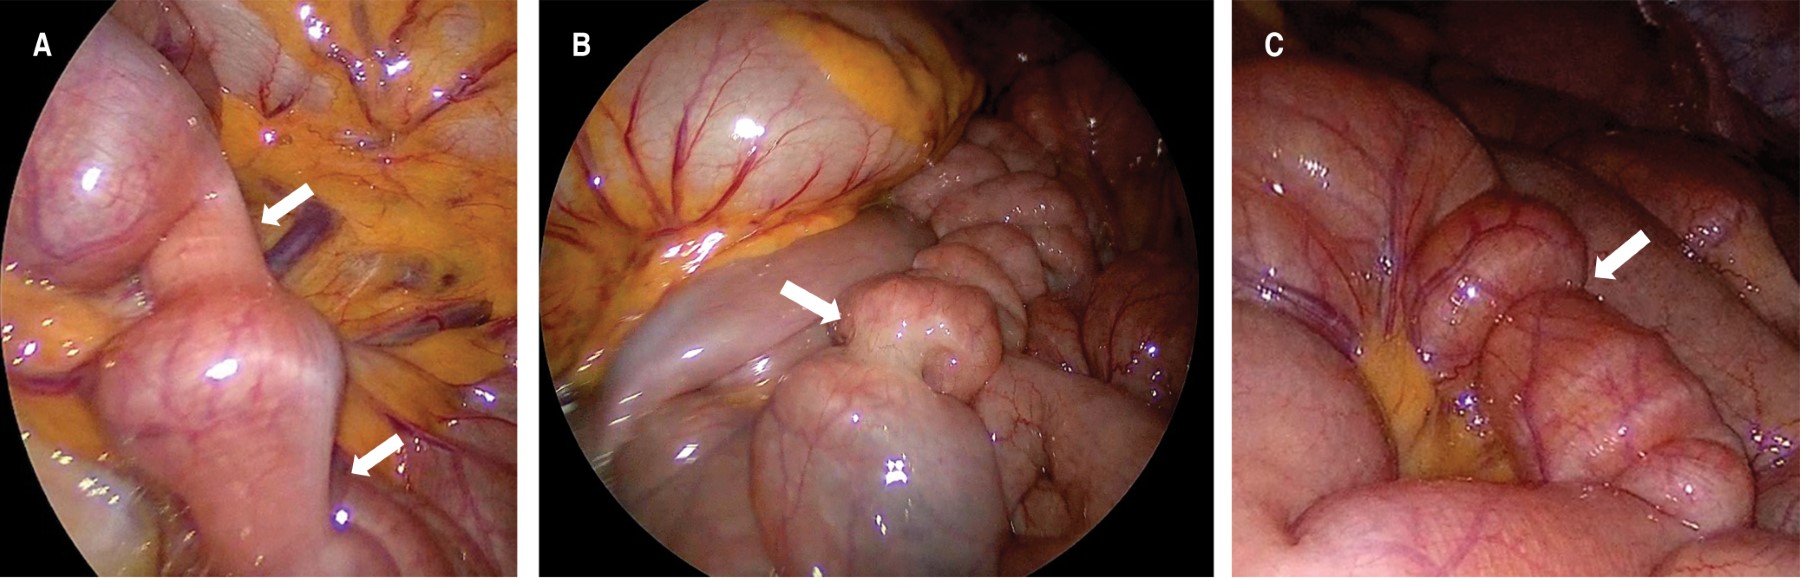

Ante dicho hallazgo radiológico se decidió realizar laparoscopía exploradora para resolver la intususcepción y valorar la viabilidad del segmento intestinal afectado. Lo primero que llamó la atención al introducir el laparoscopio fue la observación de ondas peristálticas intensas, aumentadas en frecuencia y con un patrón desorganizado e irregular en prácticamente todo el intestino delgado. Algunas de estas ondas ocurrían de forma simultánea en segmentos cortos (Figura 3A), otras eran tan intensas que parecían estenosar por completo la luz intestinal (Figura 3B) y otras parecían estar a punto de provocar intususcepciones parciales debido a la intensidad de su propulsión (Figura 3C).

Durante la exploración minuciosa de todo el trayecto intestinal no fue posible encontrar el sitio intususceptado pero sí se logró identificar un segmento yeyunal con severo edema mesentérico y congestión vascular (Figura 4A), que correspondía en localización al segmento observado en la tomografía. En esta zona también se logró apreciar una adenitis mesentérica importante (Figura 4B). Al no encontrar alteraciones en la viabilidad intestinal ni un sitio de obstrucción, se dio por terminado el procedimiento y se continuó con tratamiento médico.

Figura 3